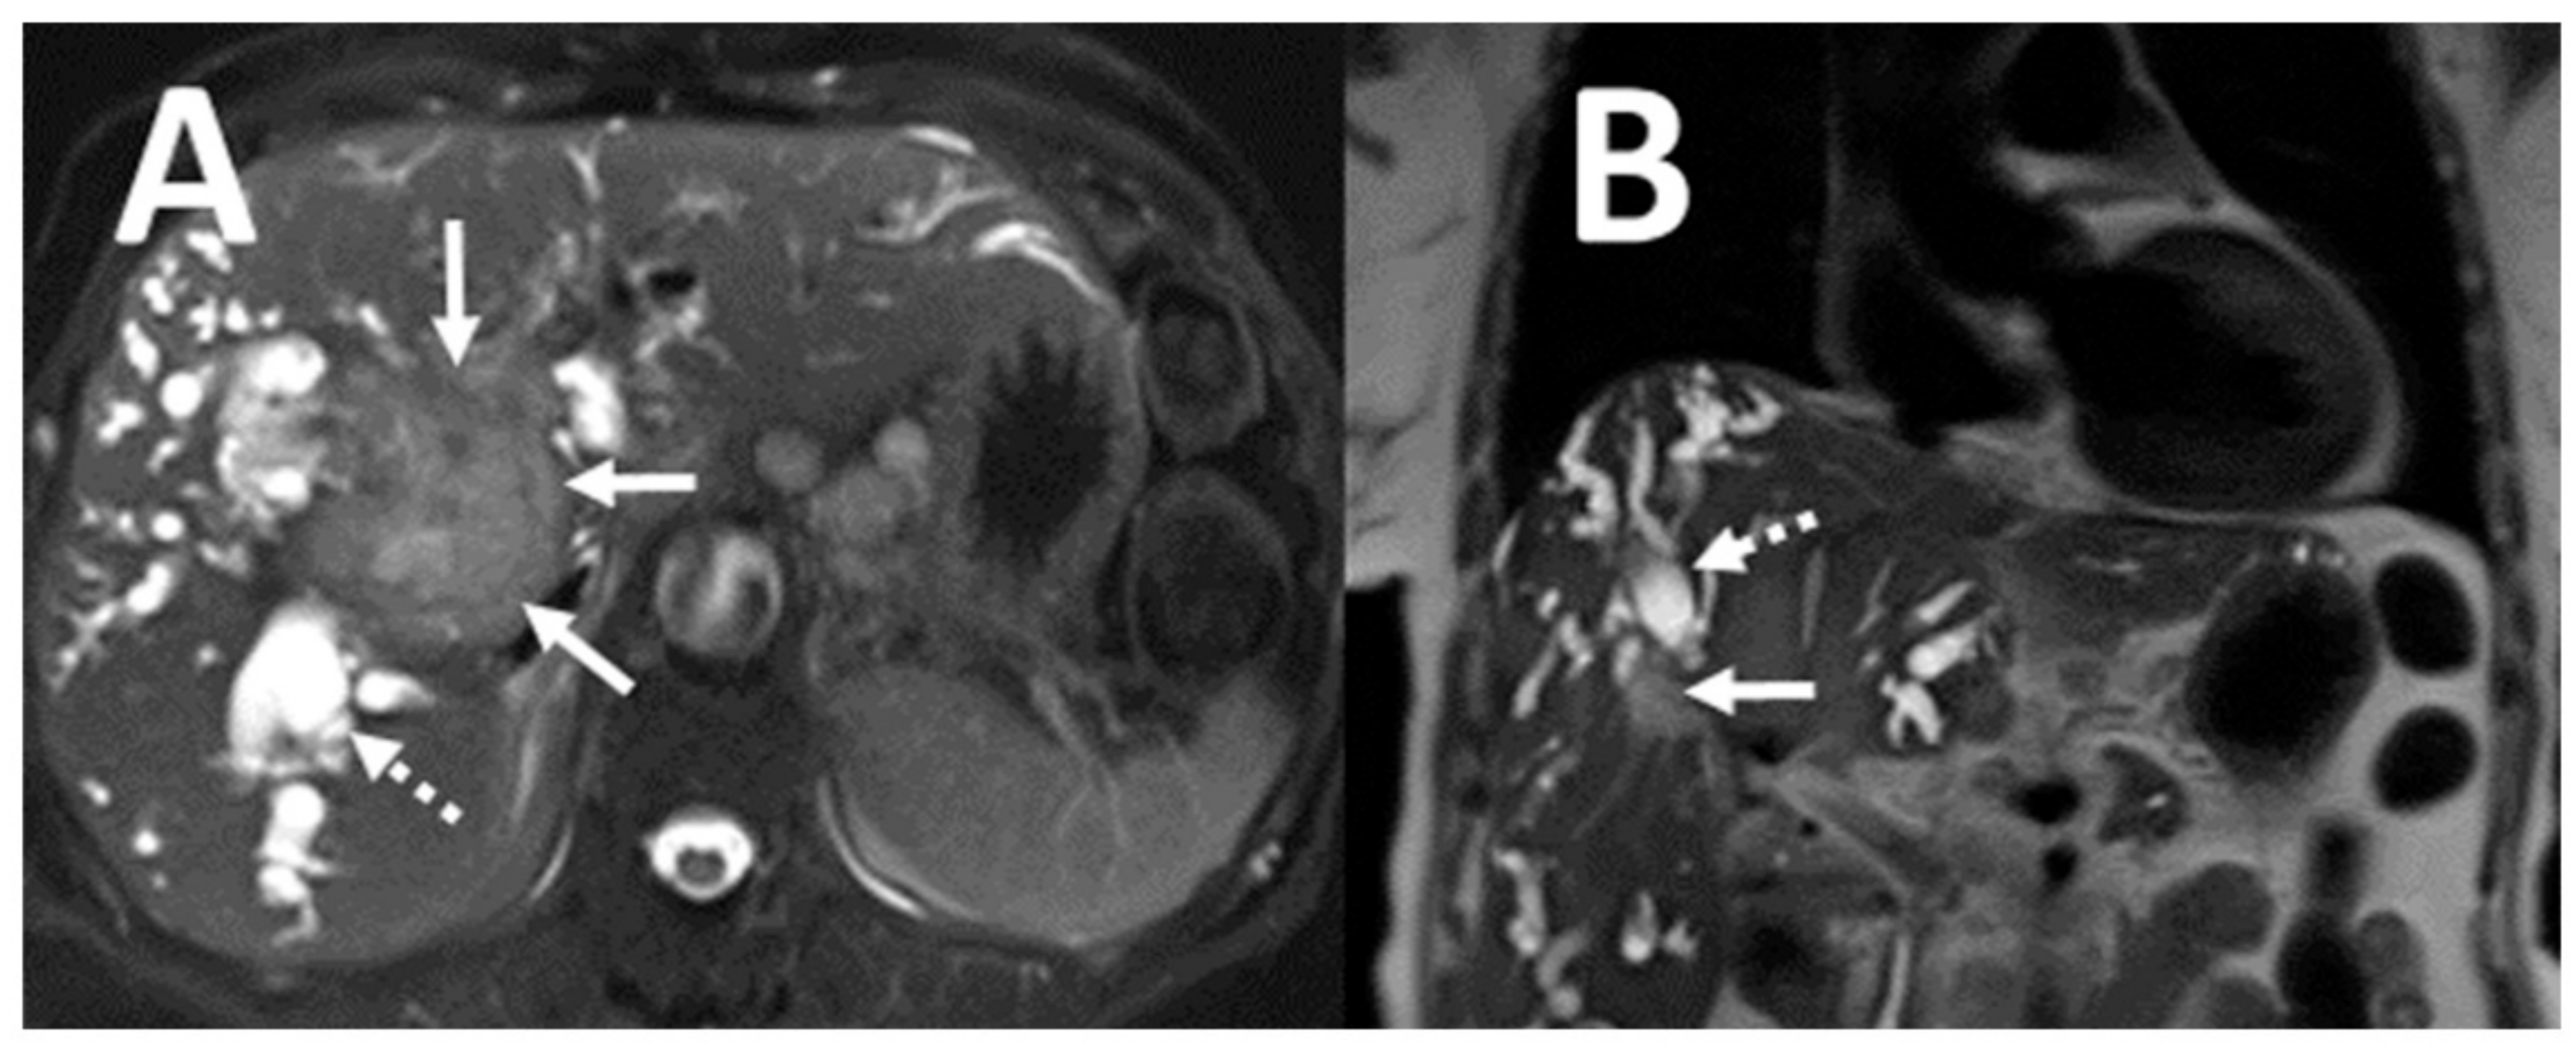

| Clinically significant NCA (n = 25) | |

| Malignancy | 18 (72) |

| Cholangiocarcinoma | 7 (28) |

| Hepatocellular carcinoma | 3 (12) |